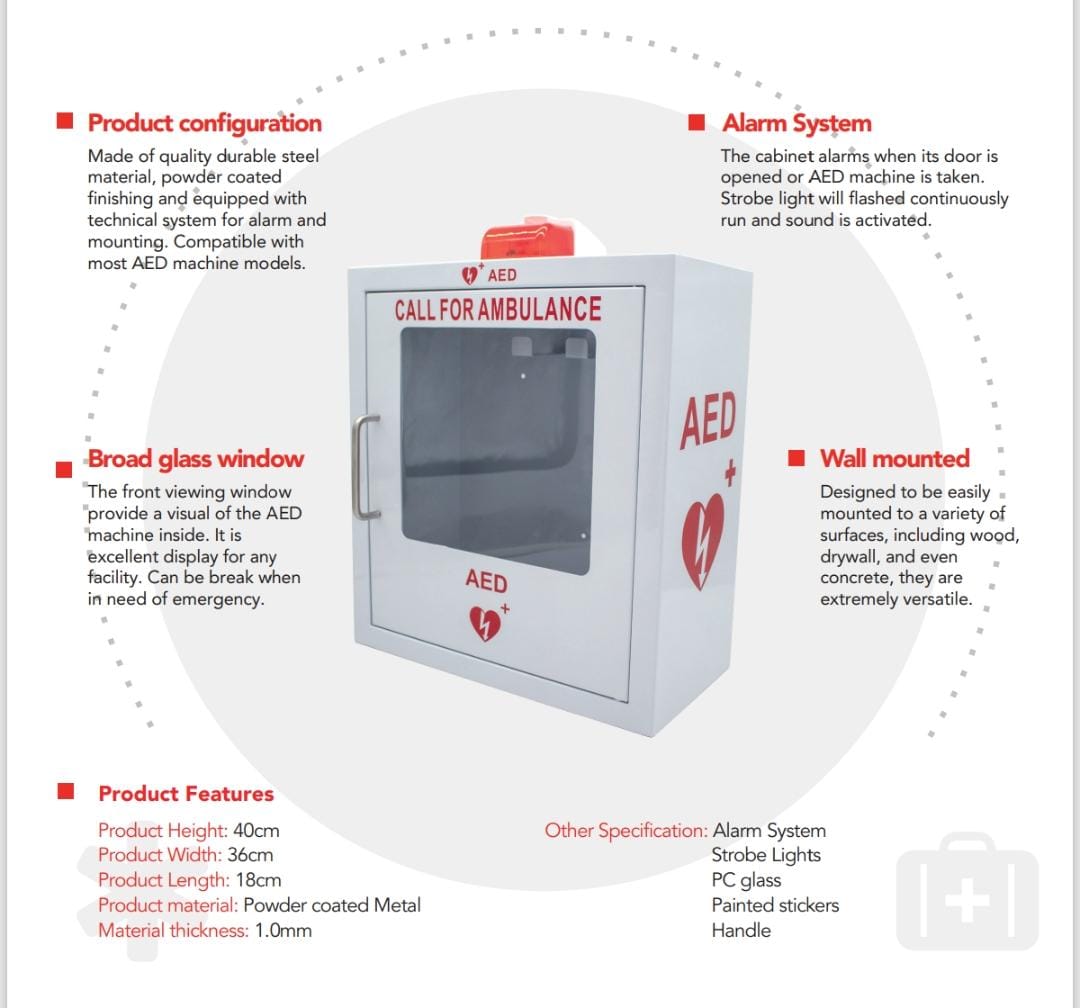

AED ALARM WALL CABINET

AED ALARM WALL CABINET